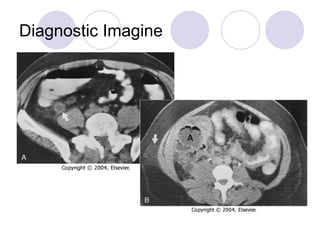

Diagnostic Imagine B-us Abdominal Plain film CT scan

Diagnostic Imagine B-usAbdominal Plain film CT scan